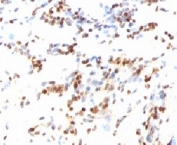

This mAb recognizes a 27kDa protein, identified as the p27Kip1, a cell cycle regulatory mitotic inhibitor. It is highly specific and shows no cross-reaction with other related mitotic inhibitors. p27Kip1 functions as a negative regulator of G1 progression and has been proposed to function as a possible mediator of TGF- induced G1 arrest. p27Kip1 is a candidate tumor suppressor gene.